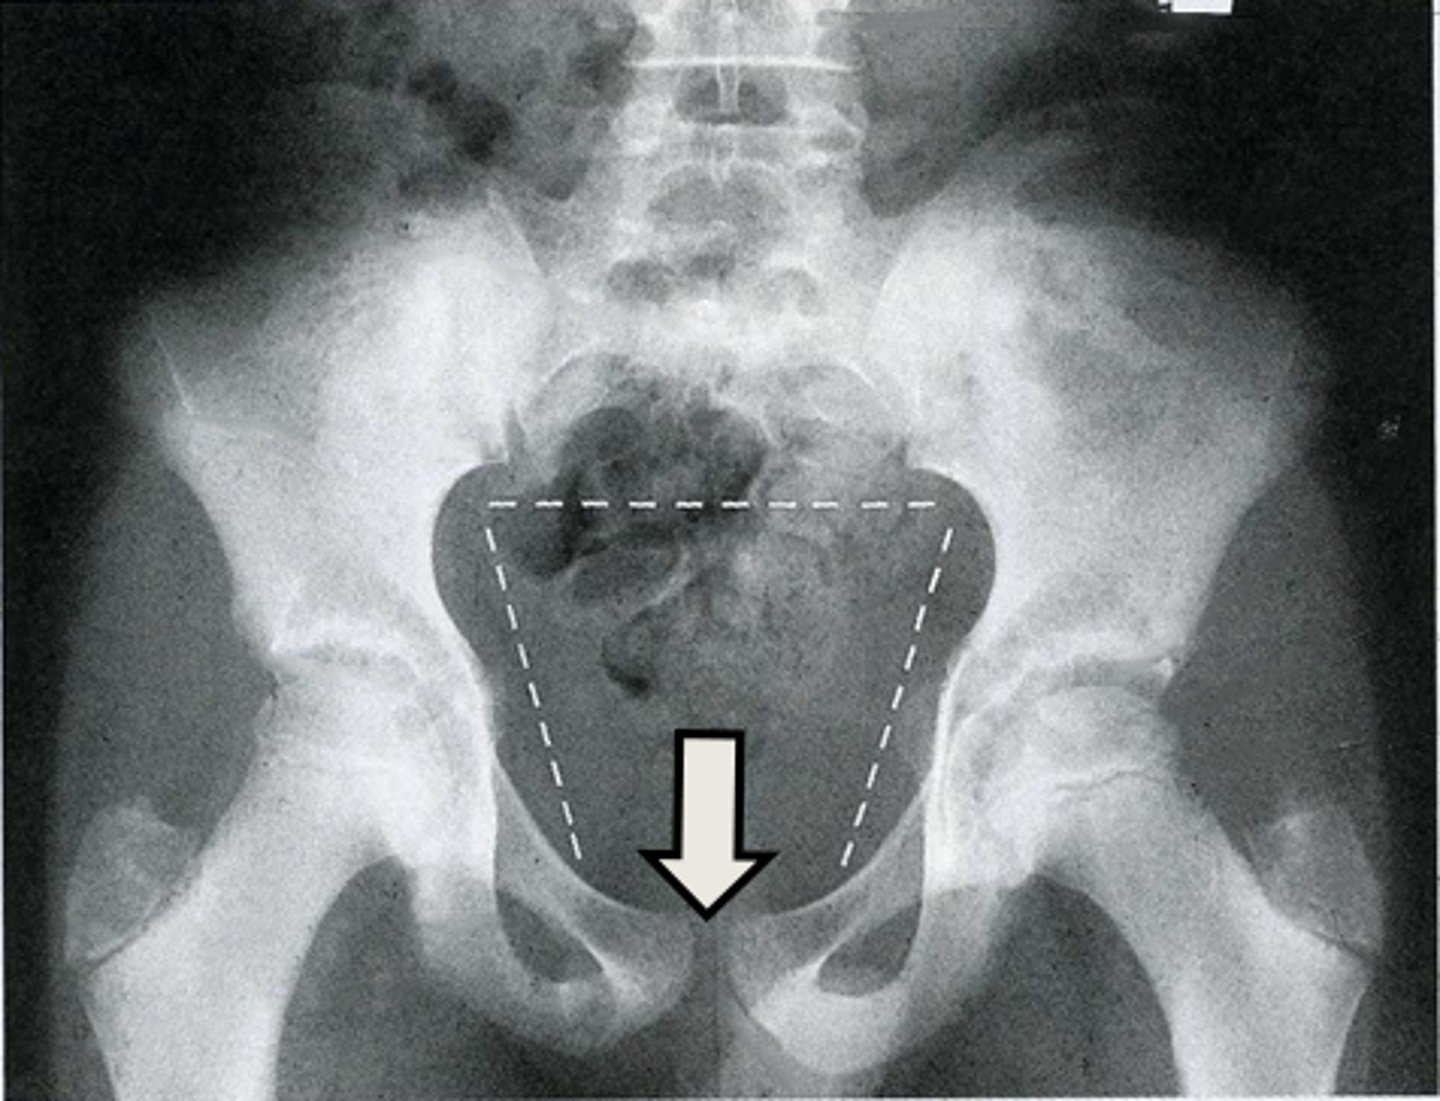

15

New cards

AP pelvis

What is the image?

<p>What is the image?</p>

16

L acetabulum

What is indicated in the image?

<p>What is indicated in the image?</p>

17

L anterior superior iliac spine (ASIS)

18

L ilium

19

L ischial tuberosity

20

L obturator foramen

21

L sacroiliac joint

22

L superior ramus of pubis

23

R acetabulum

24

R anterior superior iliac spine (ASIS)

25

R ilium

26

R ischial tuberosity

27

R obturator foramen

28

R sacroiliac joint

29

R superior ramus of pubis

30

Sacrum